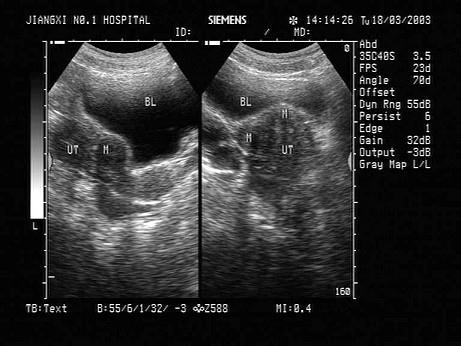

问题 女性,43岁,因月经量多,经期时间长,月经周期短就诊。体检:子宫体积大,表面不平整。结合超声图像,最可能的诊断为?(?)

选项 A.子宫内膜癌 B.宫颈癌 C.多发性子宫肌瘤 D.葡萄胎 E.子宫腺肌瘤

答案 C